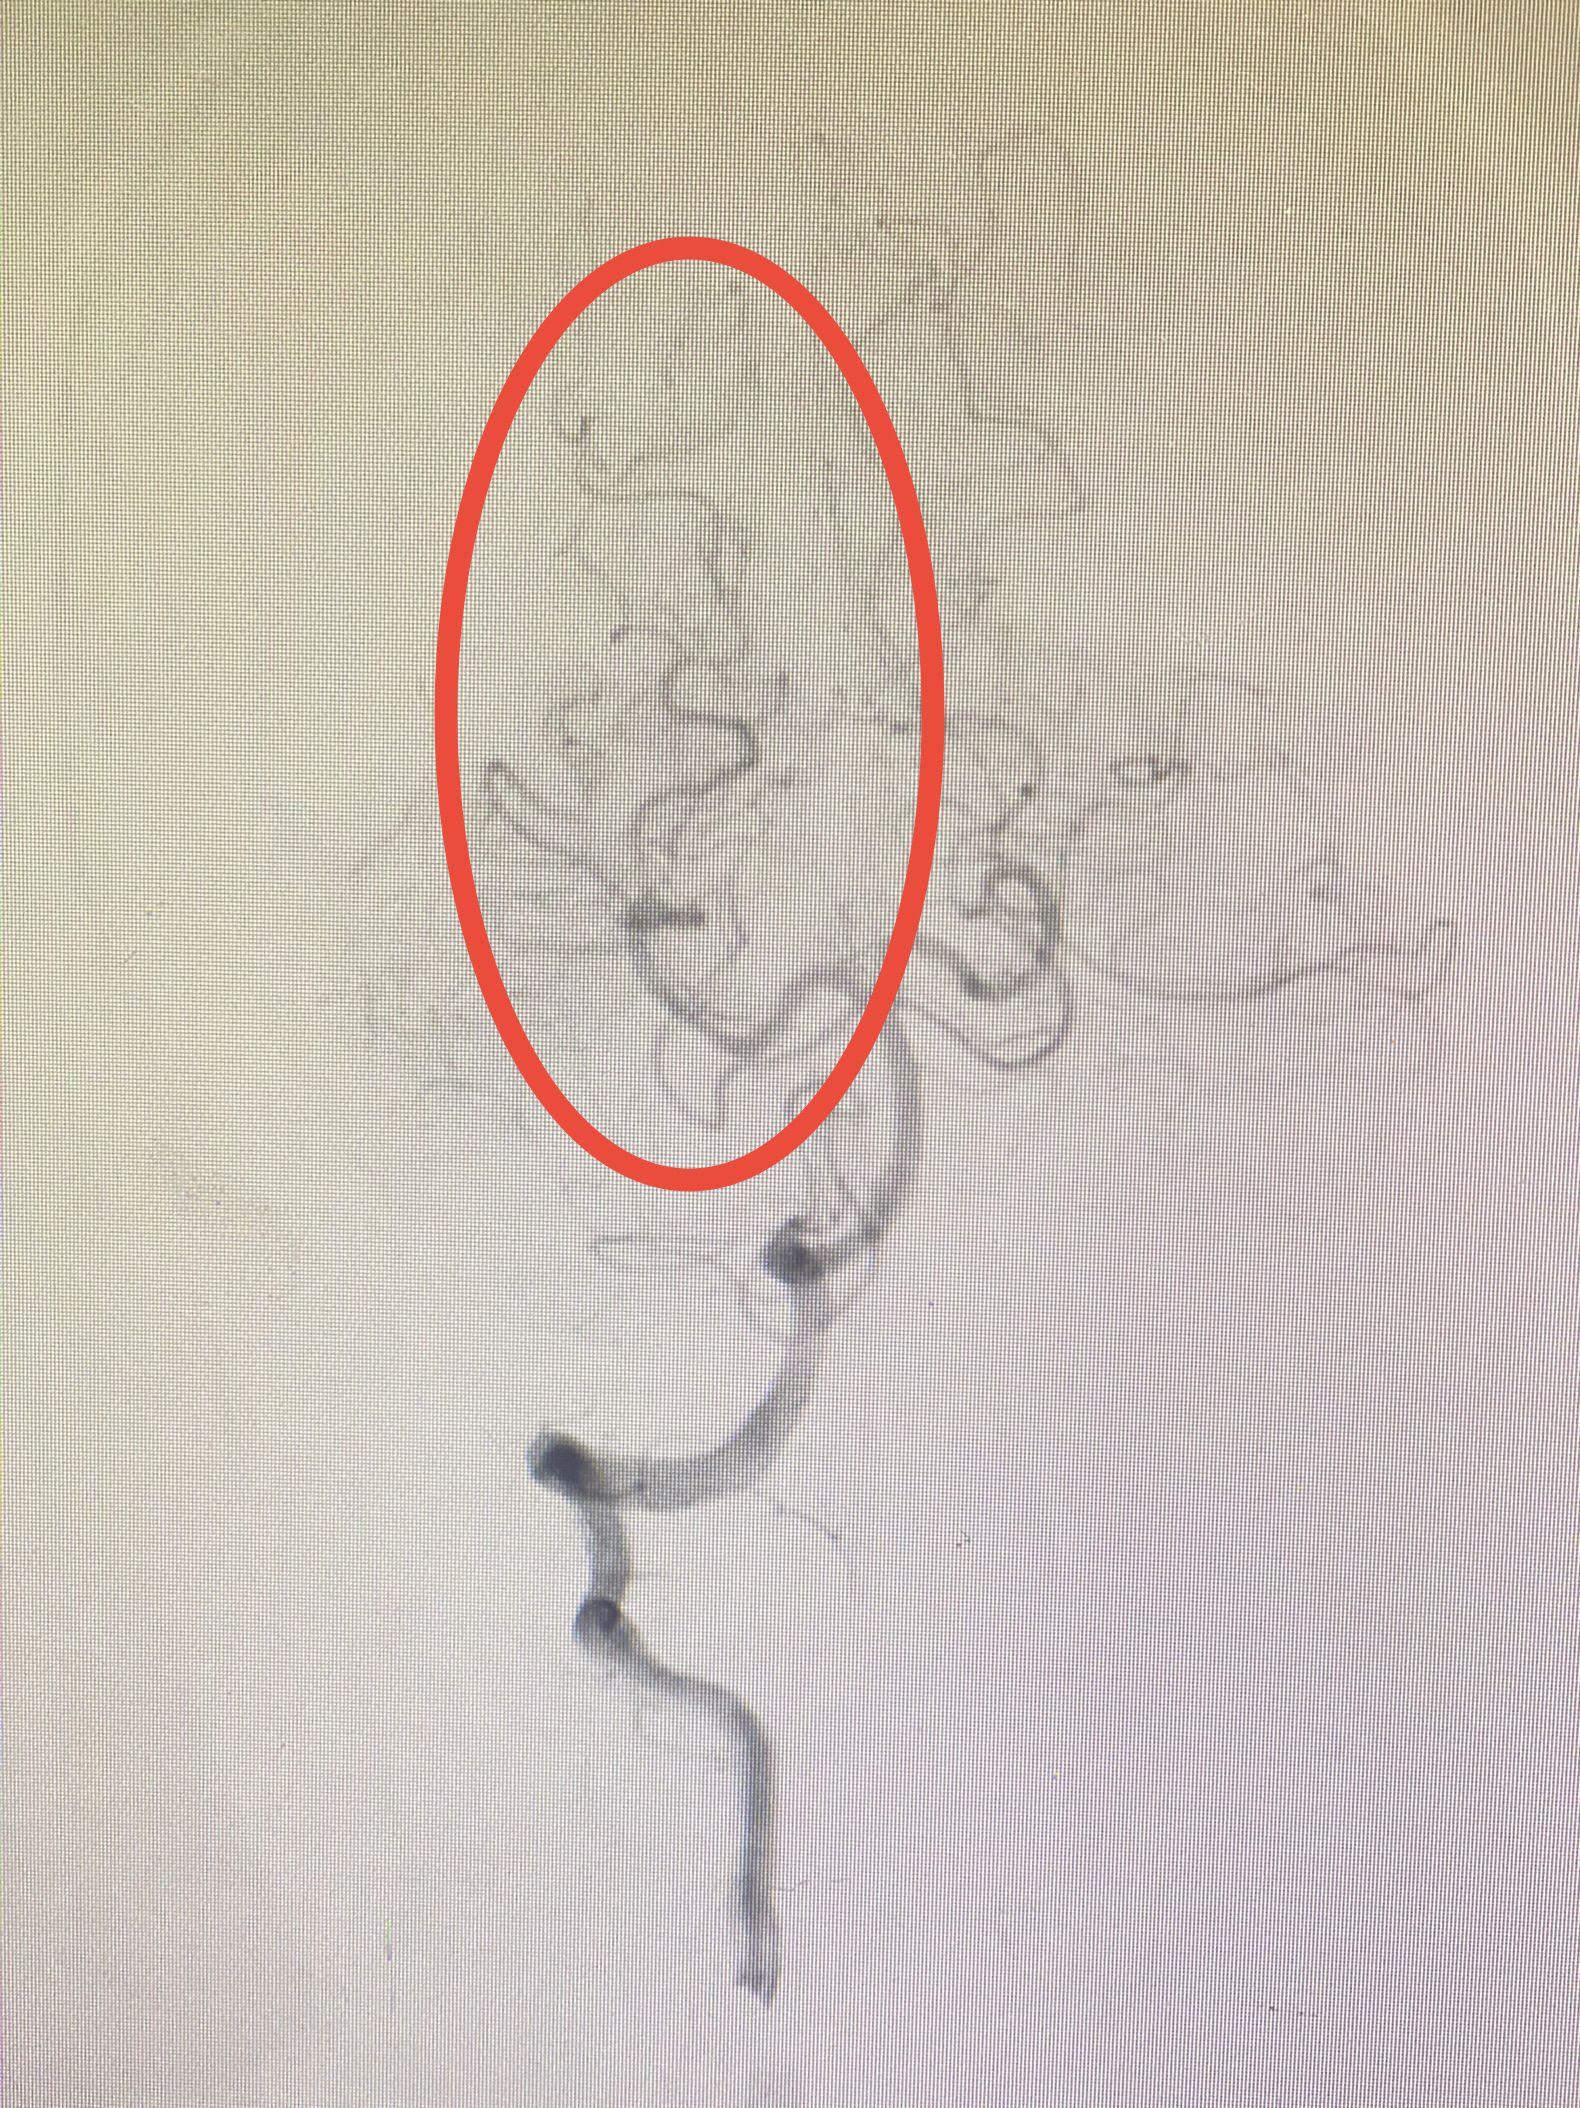

近日,神经内科介入组,在脑卒中绿道救治工作中,收治一例急性栓塞导致大脑后动脉闭塞引发丘脑梗死患者,通过介入治疗快速将血栓取出,避免病情进展加重。 患者王某,... -